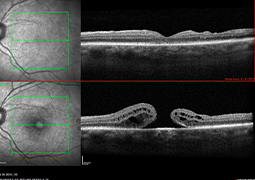

- Choroidal Neovascular Membrane in Pediatric Patients: Long-Term Outcomes of Anti-VEGF Therapy